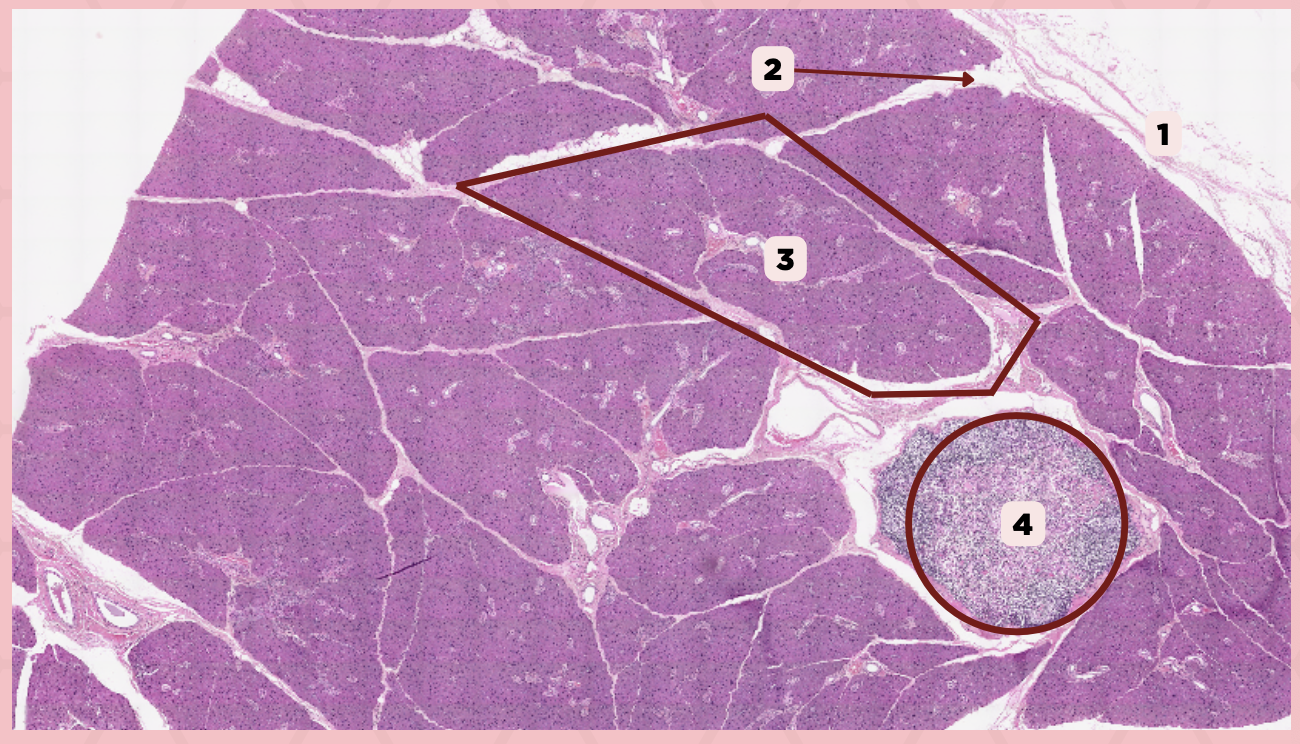

Parotid

Identify the specimen.

Capsule

Identify the structure labeled as 1.

Septa

Identify the structure labeled as 2.

Lobule

Identify the structure labeled as 3.

Lymph Node

Identify the structure labeled as 4.